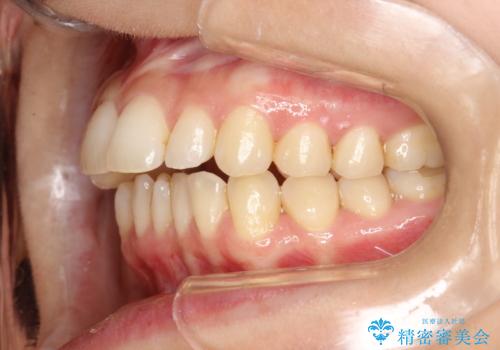

出っ歯で口が閉じずらい ワイヤーによる抜歯矯正

前歯がしっかり下がることで、上下の前歯があわさり食事もしやすくなったと言っていただきました。